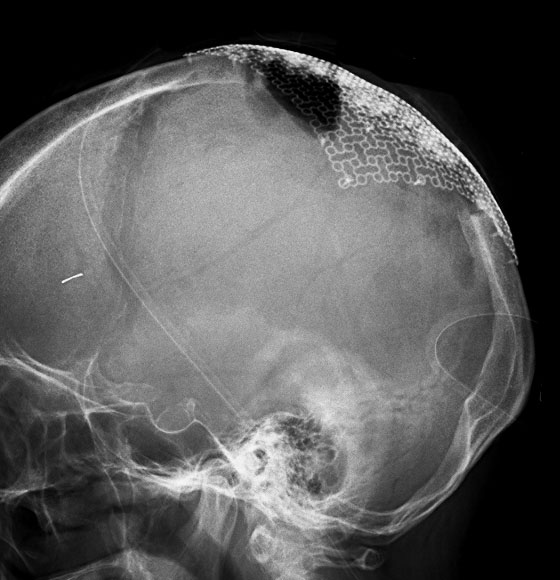

骨内髄膜腫 osseous meningioma

骨内増殖をする髄膜腫です。頭蓋骨腫瘍と間違えるようなものです。触った感じは骨腫ですが,CTでは,表面が毛羽立っていて,頭蓋冠に浸潤していることが特徴です。浅側頭動脈からの豊富な血流があります。

わずかですが頭蓋内にも腫瘍があり,硬膜が肥厚してガドリニウム増強されます。

頭蓋骨をかなり広範におかすので骨は捨てません。開頭して取り外した骨の厚くなっている部分と髄膜腫で軟らかくなっている部分を削除して,それから骨片をオートクレーブで短時間熱処理して,元あった所にもどします。下の画像は手術後1年半が経過したものですが,髄膜腫の再発はなく,熱処理骨弁は吸収されないで生着しています。